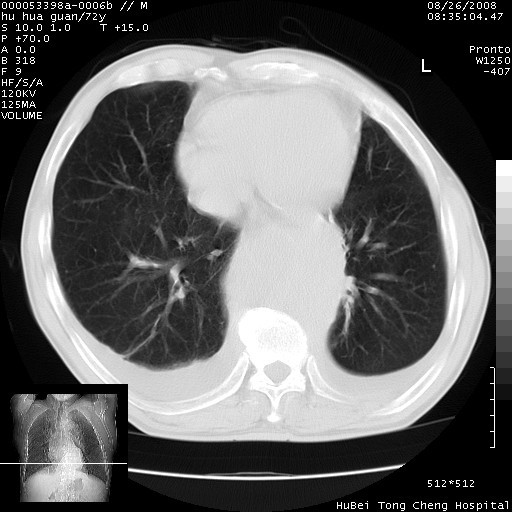

1、右上肺结节病变,肺泡癌不除外,请随诊;左下肺近后纵隔病变,考虑纵隔型肺癌侵犯大血管可能;

2、右下肺背段少许炎症,双侧胸腔积液,右下肺纤维索条。

降主动脉前移位,后纵隔占位

后纵隔占位,降主动脉前移位;双侧胸腔积液;应排外食管病变侵犯血管可能;